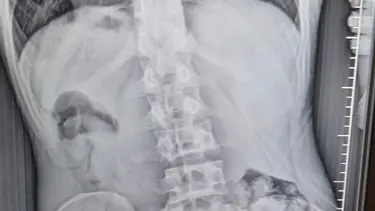

Şüphelinin yapılan iç beden muayenesi sonucunda midesinde 51 kapsül halinde toplam 309 gram metamfetamin tespit edildi.